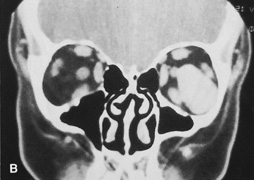

The other important consideration in planning orbitotomy is the position of the tumor within the orbit. Lesions generally may be categorized as either anterior (superficial) or posterior (deep). They can be further categorized by their relationship to the optic nerve (medial, lateral, superior, or inferior to the optic nerve). It may be helpful to further classify the location of lesions relative to adjacent anatomic structures in the orbit. Many surgeons prefer to conceptualize orbital pathologic processes as being located within one or more of seven “surgical spaces” within or around the orbit (Fig. 5). These spaces include:

Fig. 5. Axial drawing of anatomic spaces of the orbit. (1, intraconal space; 2, extraocular muscles; 3, peripheral surgical space; 4, subperiosteal space; 5, preaponeurotic space; 6, Tenon's space; 7, periorbital tissues.)

1. Central surgical space (intraconal space)

2. Extraocular muscles

3. Peripheral surgical space (extraconal space)

4. Subperiosteal space

5. Preaponeurotic space

6. Tenon's space

7. Periorbital tissues

The central surgical space is bounded by the intermuscular septum, which connects the four rectus muscles in the coronal plane. This space also is described as the retrobulbar or intraconal space, and it contains the optic nerve, intraconal fat, and various vascular and neural structures. Primary orbital tumors such as cavernous hemangiomas or optic nerve meningiomas originate in the central surgical space.

Many orbital processes involve the extraocular muscles, primarily or secondarily, making it useful to classify the extraocular muscles as residing in their own separate surgical “space.” Conditions affecting the extraocular muscles include thyroid orbitopathy, myositis, and a variety of neoplastic conditions.

The peripheral surgical space, also known as the extraconal space, lies outside the intermuscular septum but within the periorbita. This space contains a scant amount of orbital fat, the superior oblique muscle and trochlea, inferior oblique muscle, and lacrimal gland. Other important nerves and vessels extend into the space, such as the superior ophthalmic vein. A variety of pathologic processes may encroach on the peripheral surgical space.

The subperiosteal space is a potential space lying between the orbital bones and periorbita. The periorbita may provide a barrier to extension of neoplastic and infectious processes originating in the adjacent sinuses or intracranial cavity. Frequently, the subperiosteal space may fill with blood after orbital fracture or infection when associated with a paranasal sinusitis.

The preaponeurotic space is actually an anterior extension of the extraconal space. Because this space is superficial and readily accessible, sometimes it is referred to as its own orbital compartment. Frequently, neoplasms affecting the lacrimal gland, such as lymphoma, extend forward into the preaponeurotic space.

Tenon's space is a potential space between the sclera and Tenon's capsule. Tumors originating in the eye, such as choroidal melanoma, may extend into Tenon's space.

Secondary orbital tumors may arise from periorbital tissues and secondarily invade the orbit. Cutaneous malignancies arising in the eyelid or facial skin may extend posteriorly through the orbital septum, whereas nasal and paranasal sinus tumors may grow through the orbital bones into or through the subperiosteal space. Tumors arising within the cranial cavity, such as sphenoid wing meningiomas, also may affect the orbit secondarily.